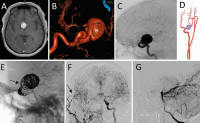

Neurovaskuläre Therapieoptionen bei komplexen Aneurysmen der Arteria carotis interna // Neurovascular therapeutic options in complex intracranial aneurysms

Journal für Neurologie, Neurochirurgie und Psychiatrie 2021; 22 (3): 128-134 Volltext (PDF) Summary Praxisrelevanz Abbildungen